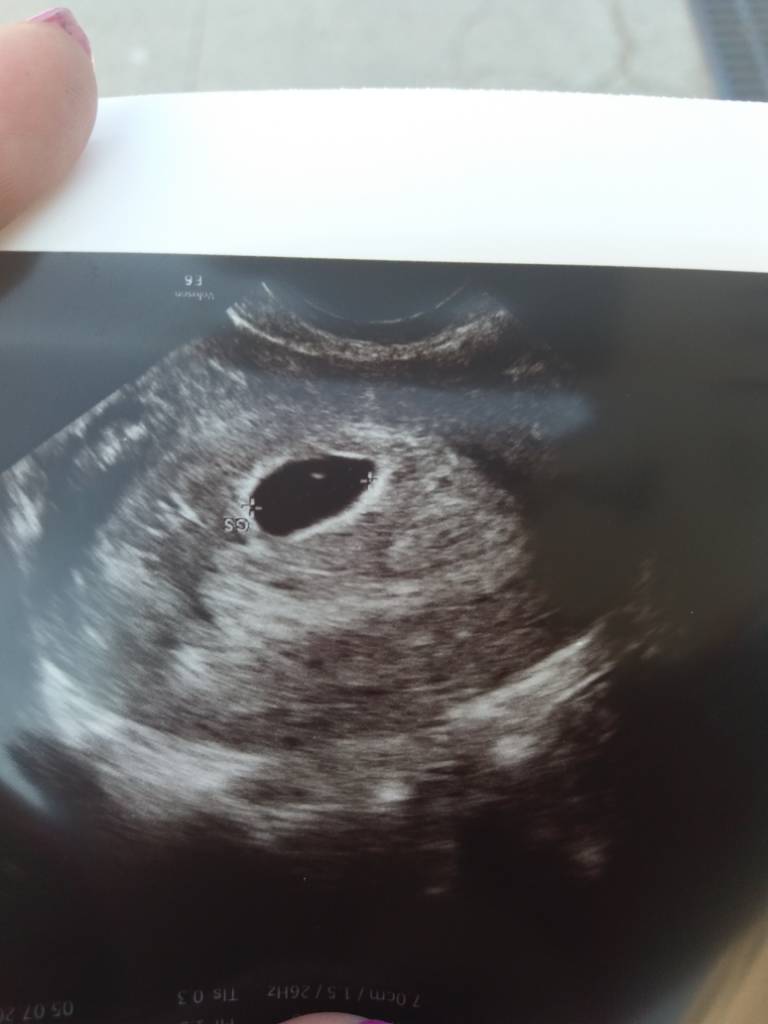

Kruszynka moja mała 12 mm [emoji173][emoji173][emoji173]

Wlasnie wracam od gina, dzis 20dpt, powiedzial ze wszystko jest tak jak ma byc i mowil ze pieknie rosnie maluch, momentalnie go zlokalizowal :) Za 2 tyg wizyta serduszkowa :)

Okazalo sie ze zostala mi jedna cysta na jajniku 2,5cm od stymulacji... On mowil ze sama zniknie, czy wam zostawaly jakies polipy czasem i co z nimi robilyscie?Zobacz załącznik 873837